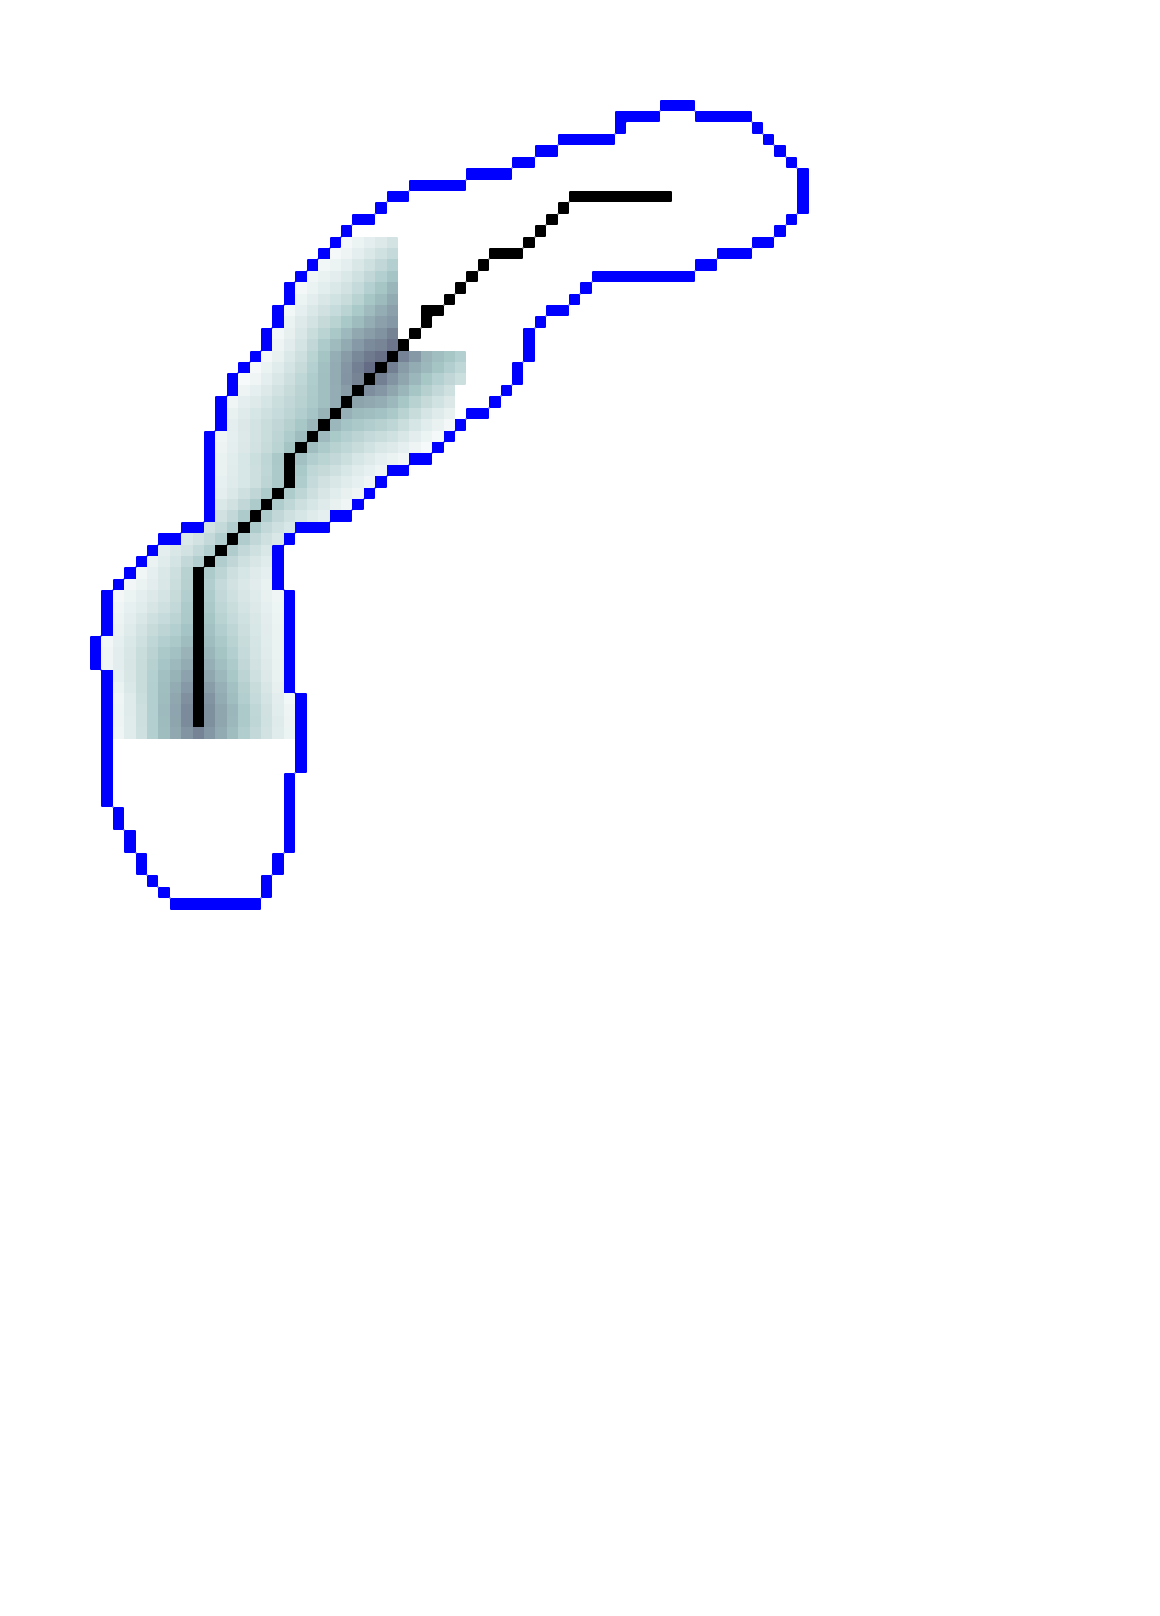

2.2.1 Anisotropic FM and Acyclic Connectivity Paradigm.

Geodesic paths are determined by back-tracing when different regions collide. The connecting geodesic is extracted minimizing at the collision grid-points. The aFM maps, i.e. ; the Voronoi index map , representing the label associated to each propagating seed; and the Tag , representing the state of each grid-point (Front, Visited, Far), are then updated within the collided regions, so that these merge as one and the front is consistent with the unified resulting region. This is continued until all regions merge.

Initialization. The seeds are aligned towards the vessels’ mid-line with a constrained gradient descent, resulting in an initial set of sources . All 26-connected components initialize the aFM maps, i.e., , , , and constitute also the initial geodesics .

Fast Marching Step. The aFM maps are updated by following an informative propagation scheme. We refer to [4] for the 3D aFM step considering the 48 simplexes in the 26-neighbourhood of the Front grid-point with minimal .

Path Extraction. Collision is detected when Visited grid-points of different regions are adjacent. A connecting is determined by linking the back-traced minimal paths from the collision grid-points to their respective sources with a gradient descent on (fig. 2). The associated integral geodesic length is computed and the connectivity in is updated in the form of an adjacency list. Lastly, the grid-points of the extracted are further considered as path seeds in the updating scheme, since furcations can occur at any level of the connecting minimal paths.

Fast Updating Scheme. A nested aFM is run only in the union of the collided regions using a temporary independent layer of aFM maps, where , , and . Ideally, the nested aFM is run until complete domain exploration, however, to speed up the process, the propagation domain is divided into the solved and unsolved sub-regions, and the update is focused on the latter (fig. 2). The boundary geodesic values of equal the geodesic distances at the collision grid-points. Lastly, the aFM maps are updated as: , , and .

3.2 Connected Geodesic Paths as Vascular Tree

Representative examples of degraded synthetic images from SVT and the respective GT are shown in fig. 4 together with the connected graphs extracted by VTrails. Analogously, the same set of images are reported for the real images TOF and CTA in fig. 4. Qualitatively, the extracted set of connected geodesic paths shows remarkable matching with the provided GT in all cases. First, we verify the acyclic nature of the graph. We found no cycles, degenerate graphs and unconnected nodes, meaning that the extracted connected geodesic paths represent a connected geodesic tree. Precision and recall are then evaluated for the identified branches. Also, error distances are determined as the connected tree’s binary distance map evaluated at GT. Average errors () precision and recall are reported (meanSD) in table 1. Note that no pruning of any spurious branches is performed in the analysis.